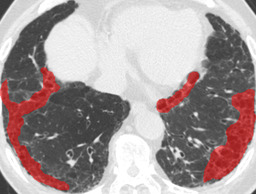

Figure 1: Typical slices for each DLD classes. Slices of HRCT are shown in lung window setting (window-center=-600, window-width=1500) with annotated labels superimposed in transparent colors. Note that even if more than one DLD patterns existed, only one DLD pattern was chosen and annotated for a slice to facilitate the annotation process.

Figure 4: Average results and dice coefficients for each DLD pattern. Automated segmentation results are superimposed with colors. For each DLD pattern, the slice that gave the median dice coefficient for the proposed method with λ=0.1𝜆0.1\lambda=0.1 was chosen to represent the average result. Note that although CNN performed multi-class segmentation, only one DLD pattern per slice was taken into account for the evaluation.